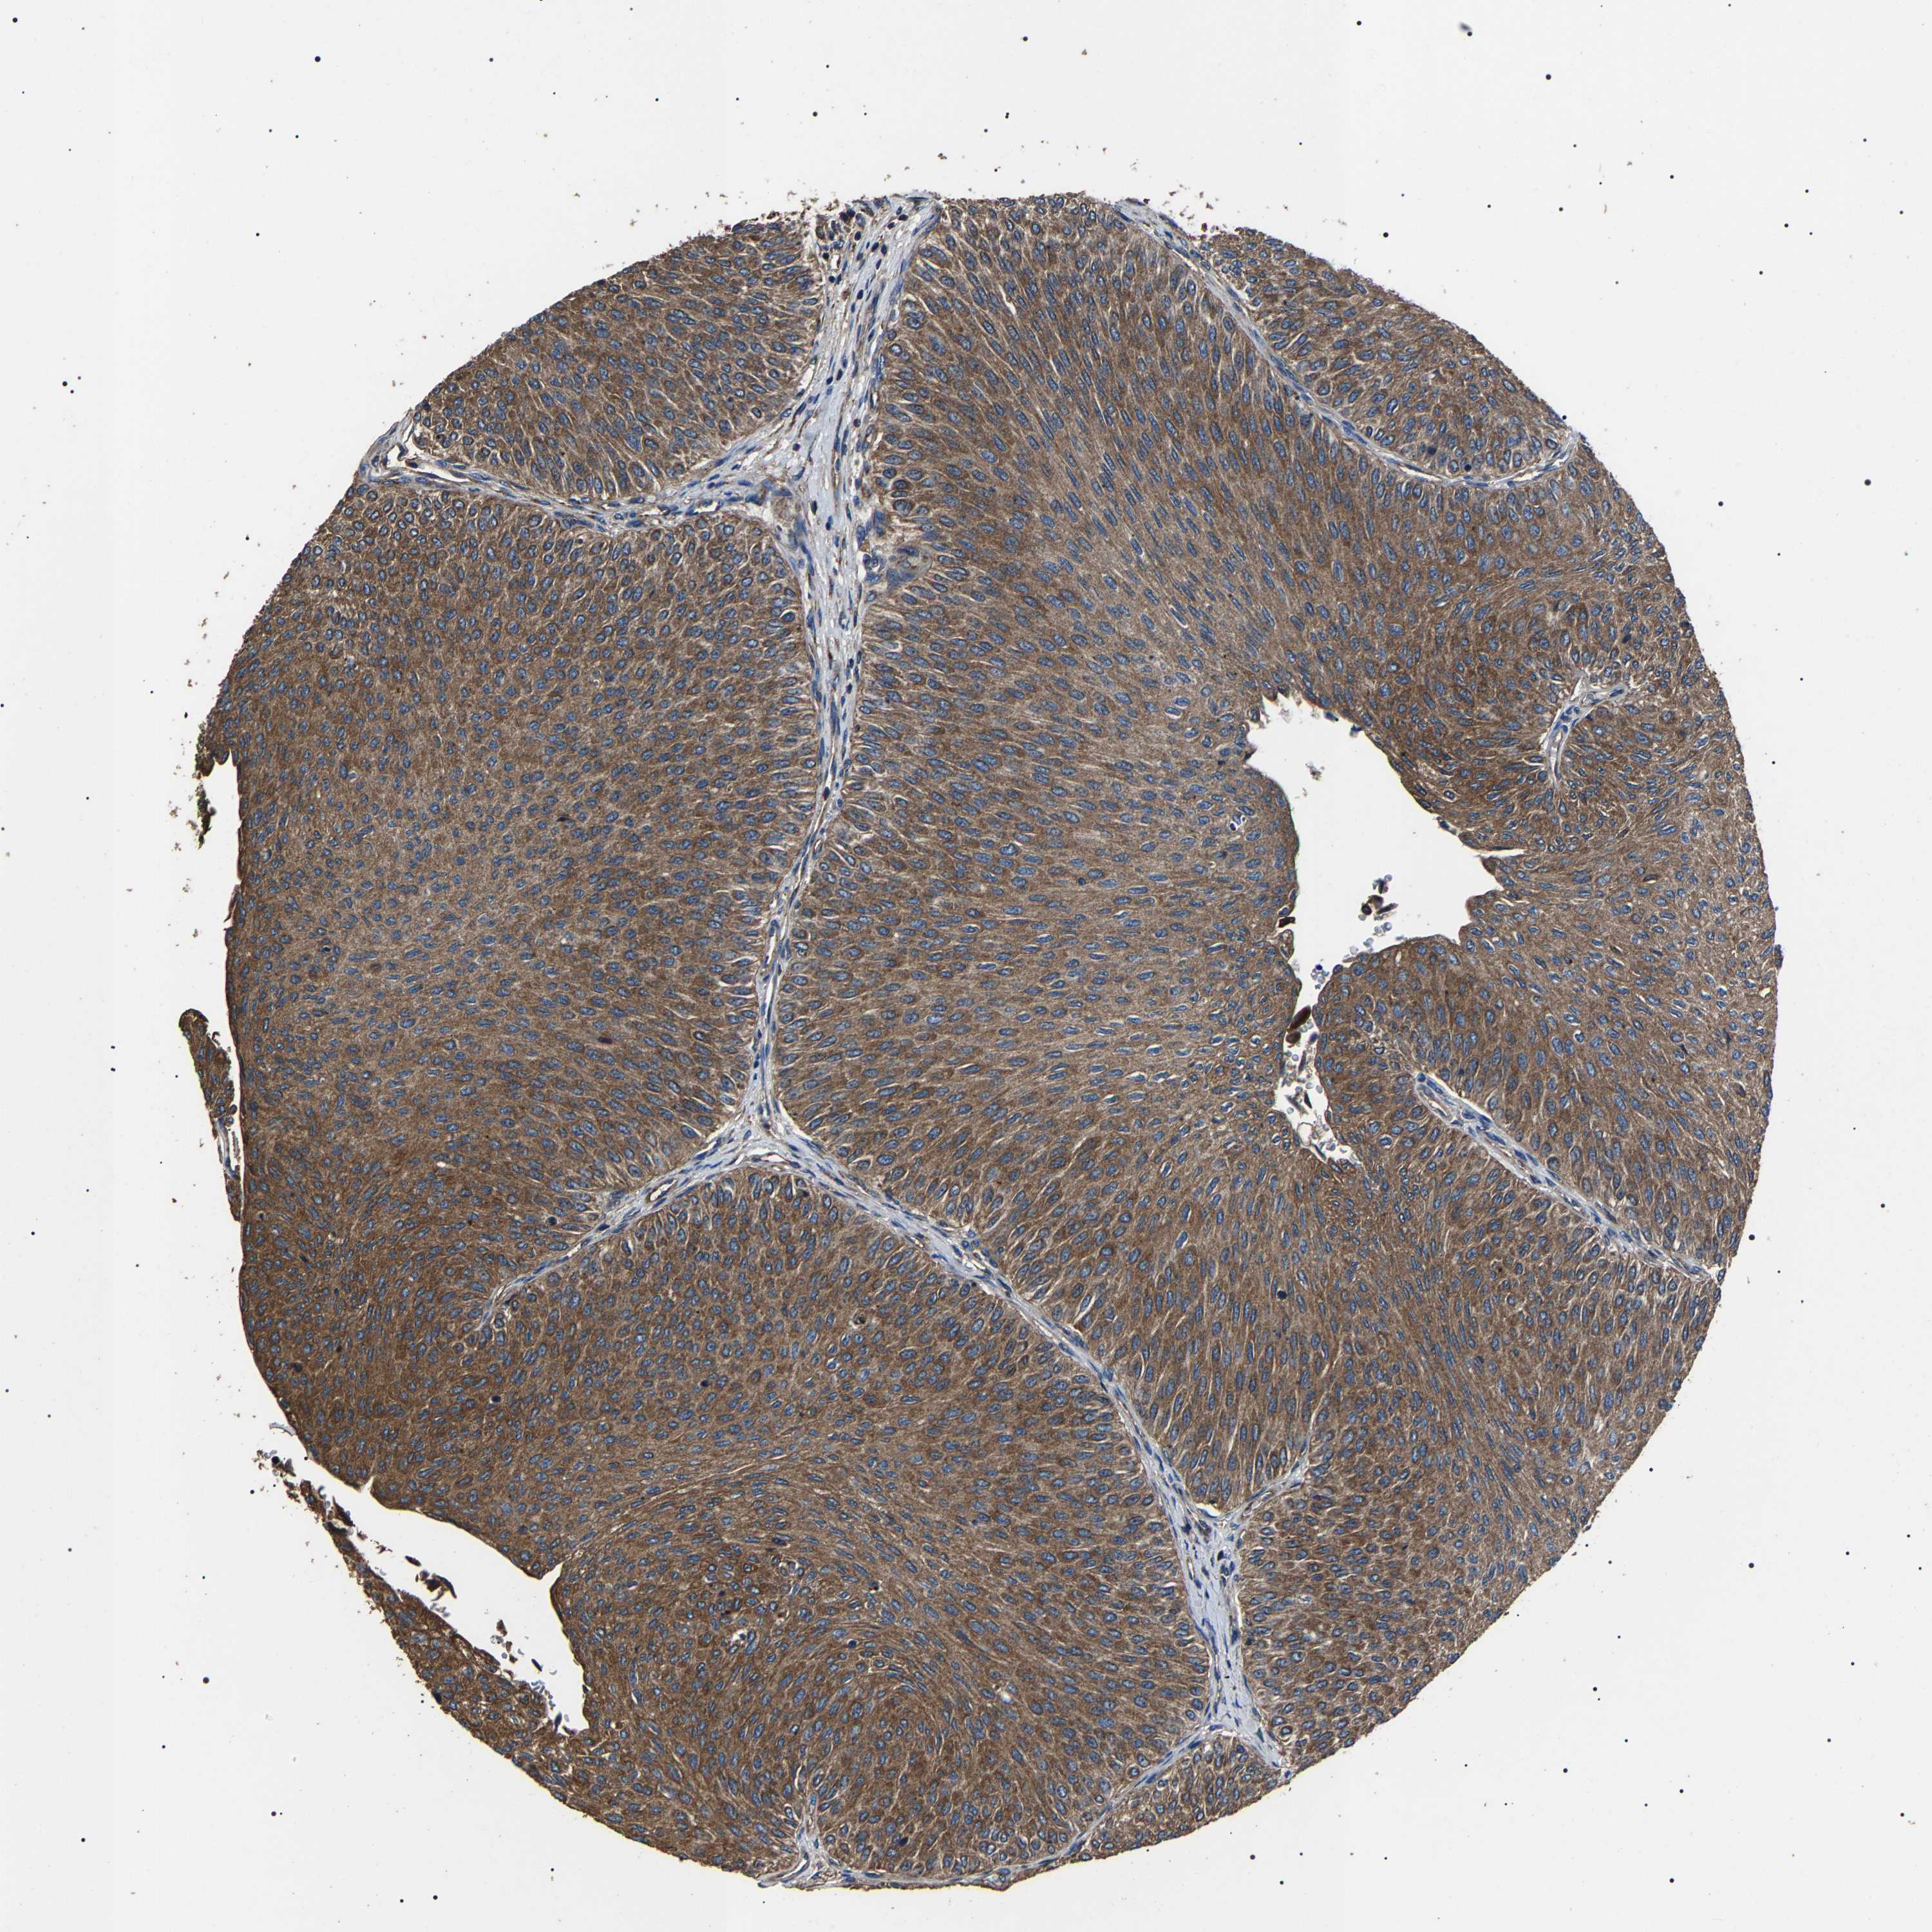

UROTHELIAL CANCER - Protein expressioni

A mouse-over function shows sample information and annotation data. Click on an image to view it in a full screen mode. Samples can be filtered based on level of antibody staining by selecting one or several of the following categories: high, medium, low and not detected. The assay and annotation is described here.

Antibody stainingi

Antibody staining in the annotated cell types in the current human tissue is reported as not detected, low, medium, or high, based on conventional immunohistochemistry profiling in selected tissues. This score is based on the combination of the staining intensity and fraction of stained cells.

Each image is clickable and will lead to virtual microscopy that enables deeper exploration of all samples and also displays staining intensity scores, fraction scores and subcellular localization as well as patient and tissue information for each sample.

Antibody HPA018447

Staining

High

Medium

Low

Not detected

Intensity

Strong

Moderate

Weak

Negative

Quantity

>75%

75%-25%

<25%

None

Location

Nuclear

Cytoplasmic/membranous

Cytoplasmic/membranous,nuclear

Urothelial carcinoma, Low grade

Urothelial carcinoma, High grade